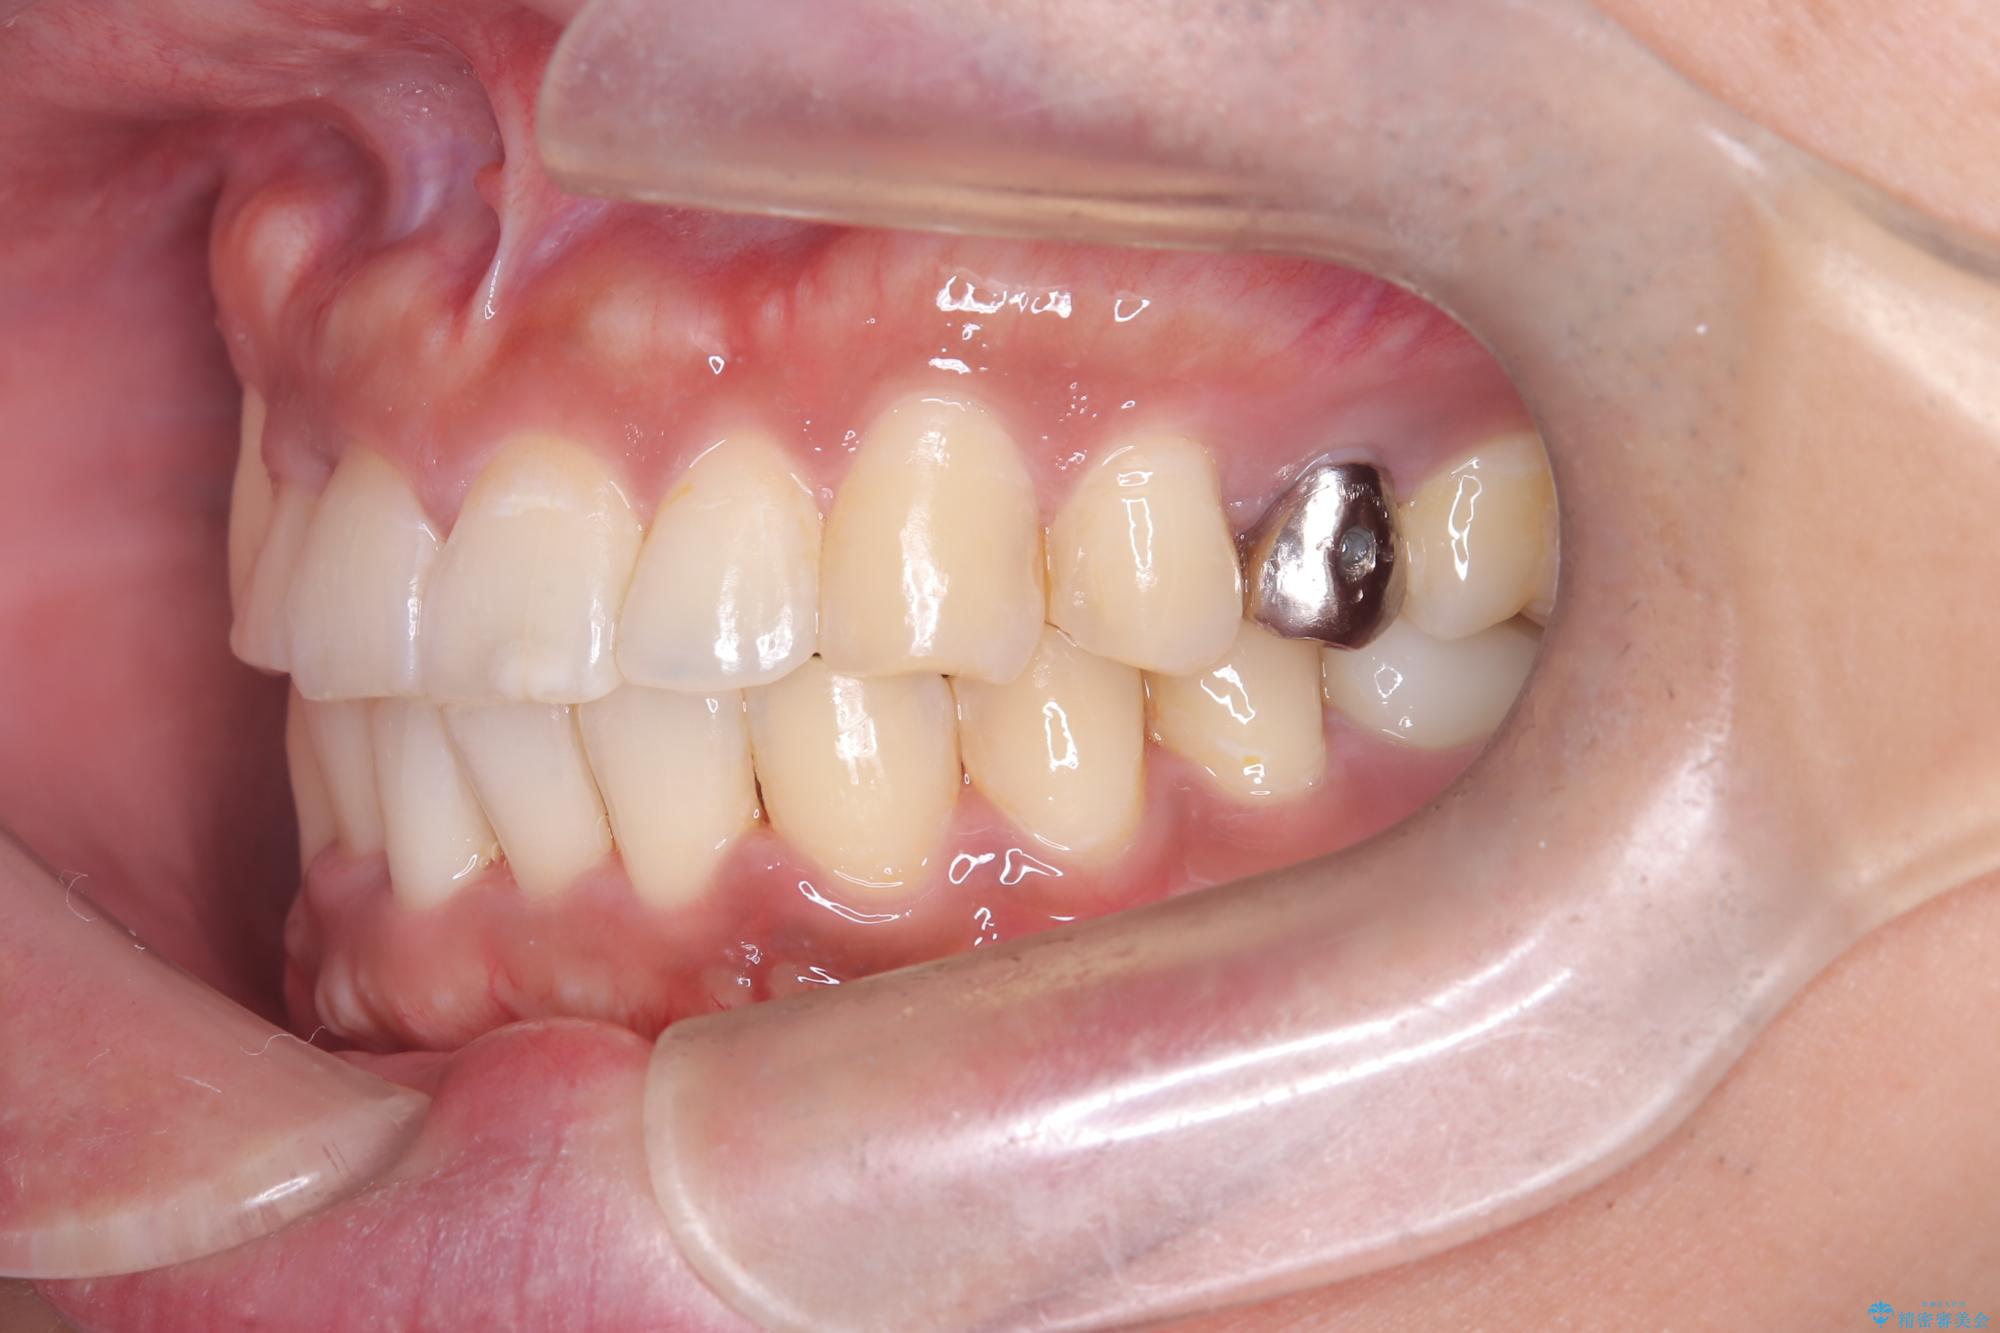

【ワイヤー矯正】八重歯と下の歯の凸凹を治したい

- 主訴:右上の八重歯と、下の歯の凸凹を治したい

上顎右側第一小臼歯と下顎右側第一小臼歯を抜歯しワイヤー矯正を行いました。

右側2級、左側1関係だったため、右側上下第一小臼歯を抜歯し、ワイヤー矯正を行いました。